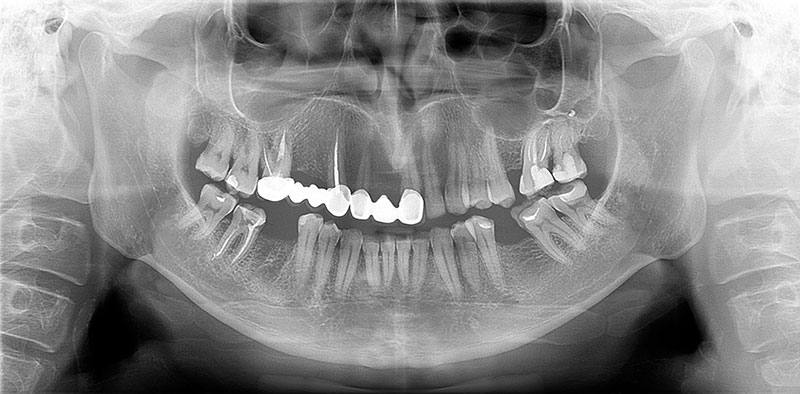

インプラント治療の成否は、手術そのものではなく、術前の診査、診断にかかっております。インプラントを骨に埋入するだけであれば、技術的には多くの歯科医師が行うことが可能です。

しかし、長期的に安定し、自然な咬合と調和した結果を得るためには、骨や歯茎の状態、咬合関係、顔全体のバランスを的確に評価する力が欠かせません。

当院では、術前の診断と治療設計を最も重視し、科学的根拠に基づいた分析を行った上で、すべての工程を論理的かつ精密に進めております。また、患者様にはCT画像やシミュレーションを用いた詳細な提案資料をお渡しし、治療内容を明確にご理解頂けるよう努めております。

STEP02精密検査

無料相談後、インプラント治療をご希望される方は、後日CT撮影を含む精密検査を実施致します。

骨の厚みや神経、血管の位置などを3次元的に解析します。